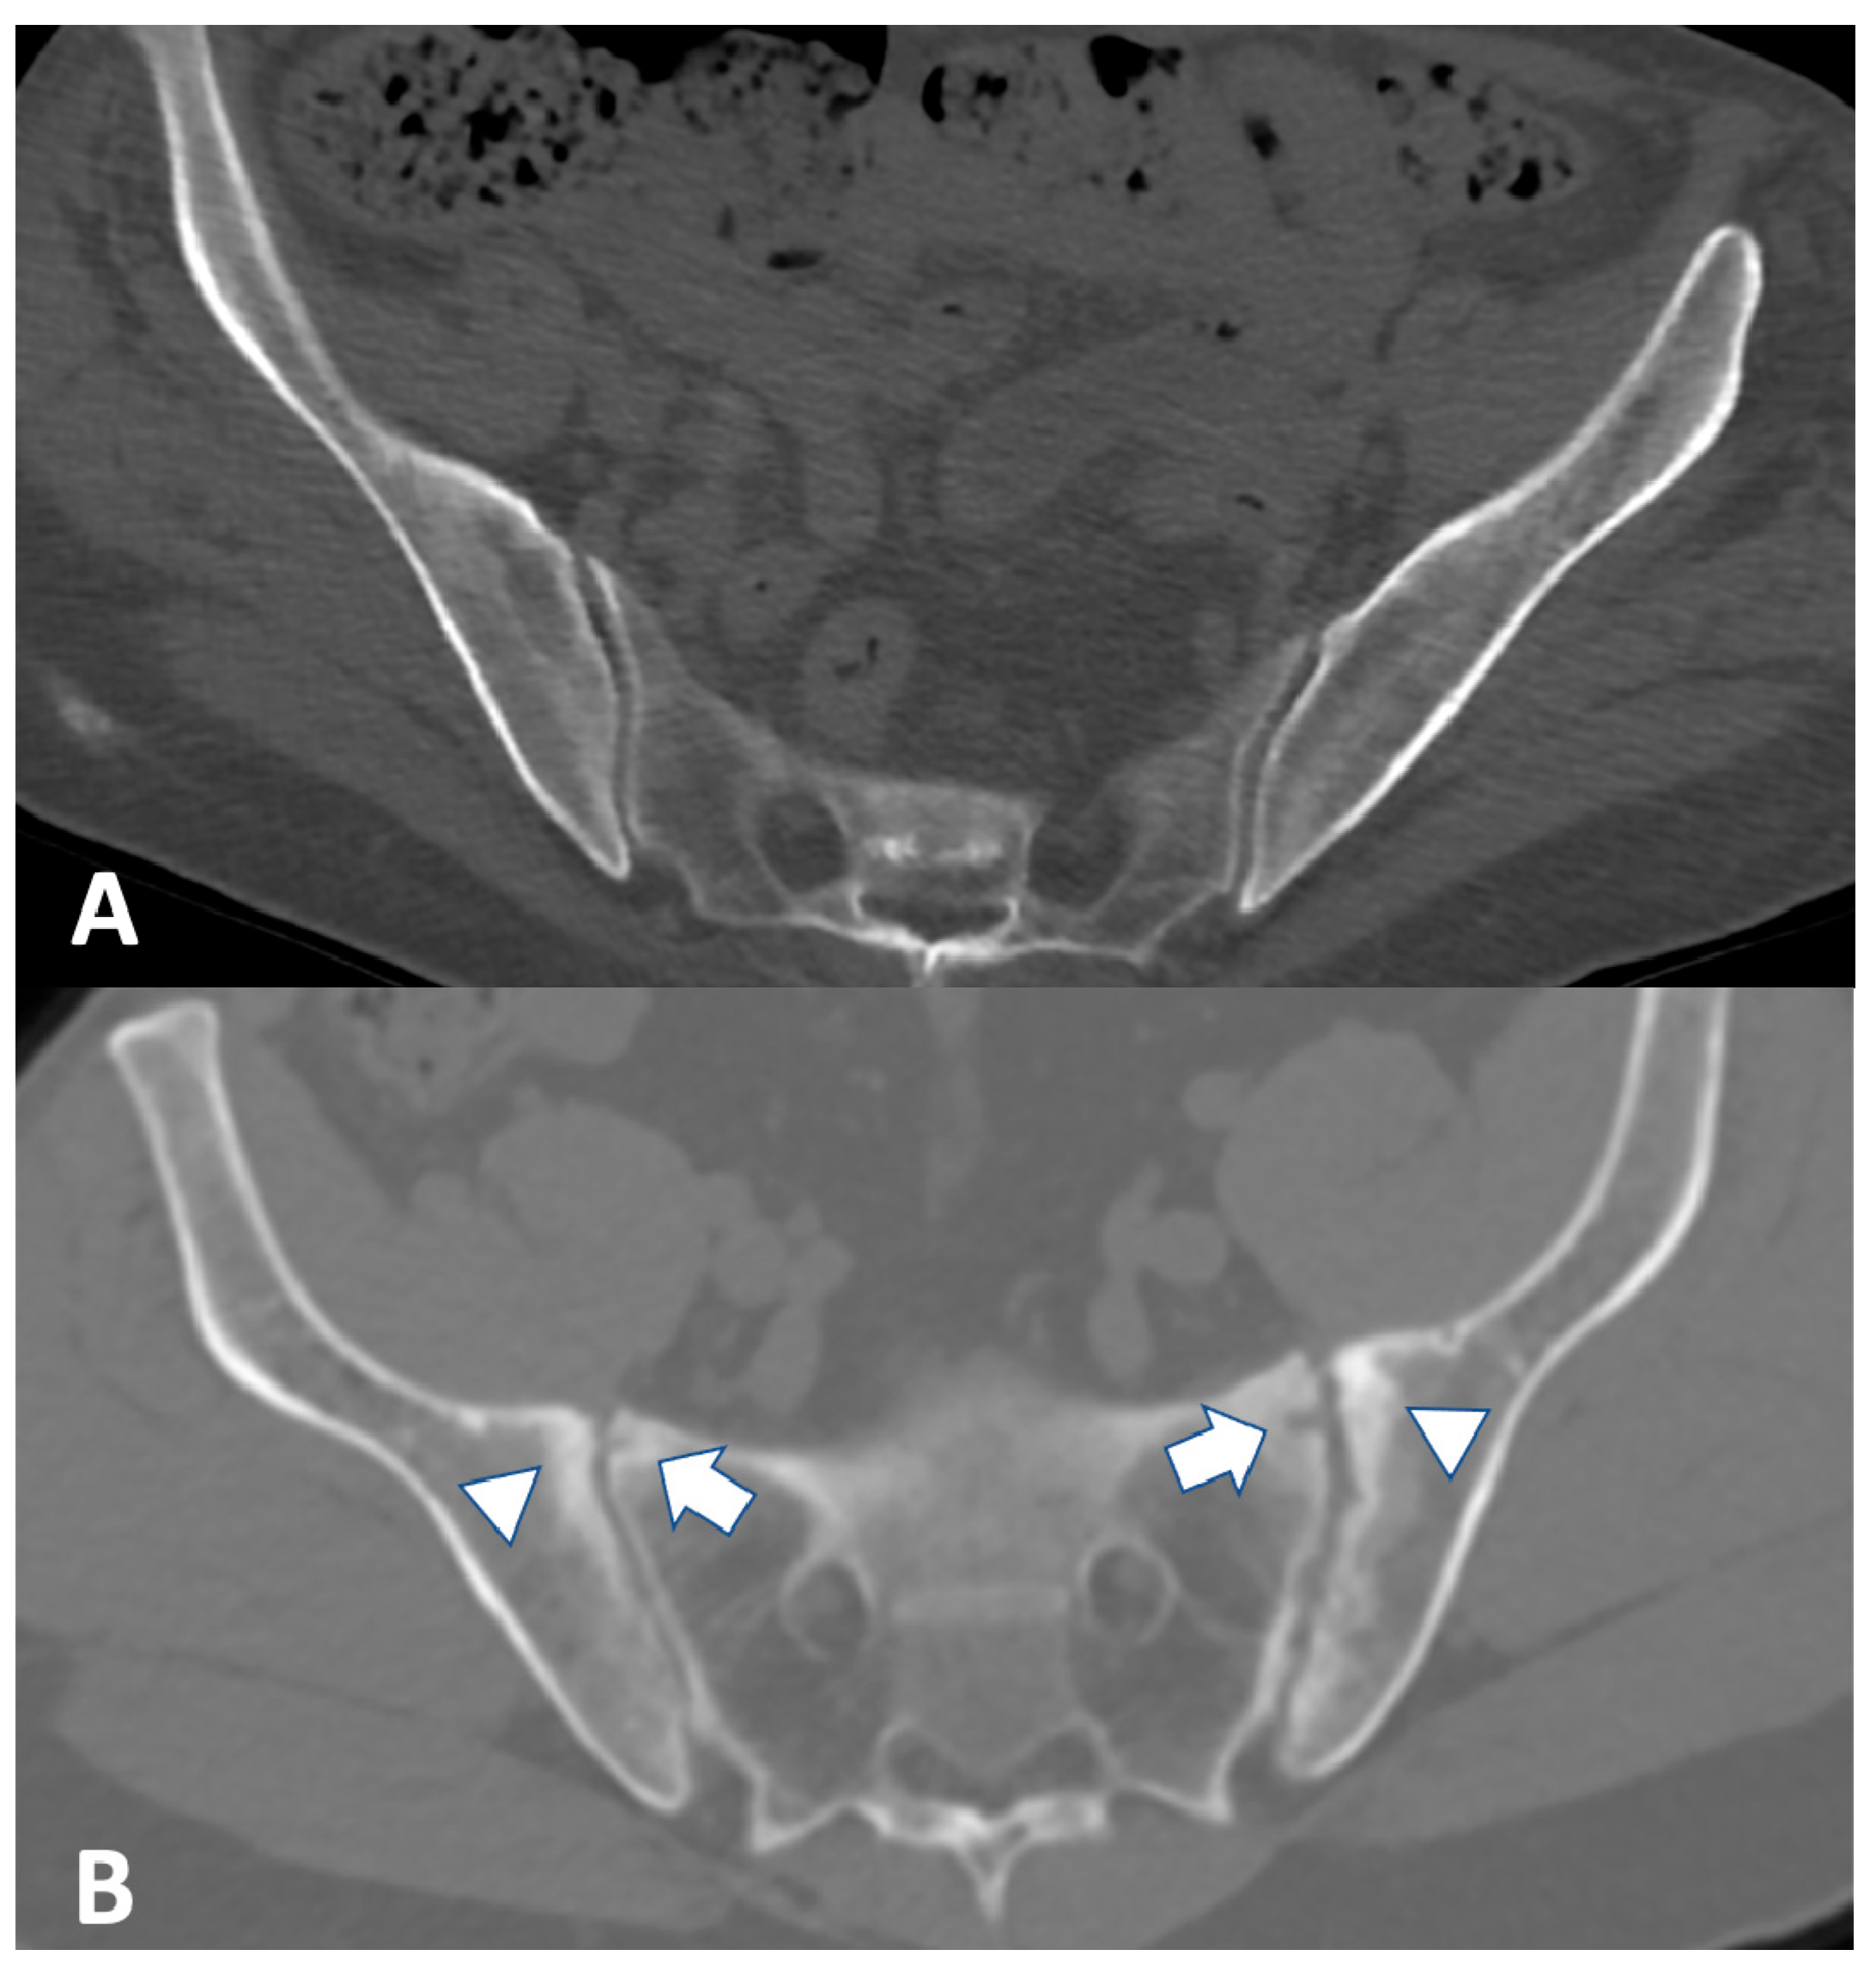

2.3. Computed Tomography

2.4. Ultrasound